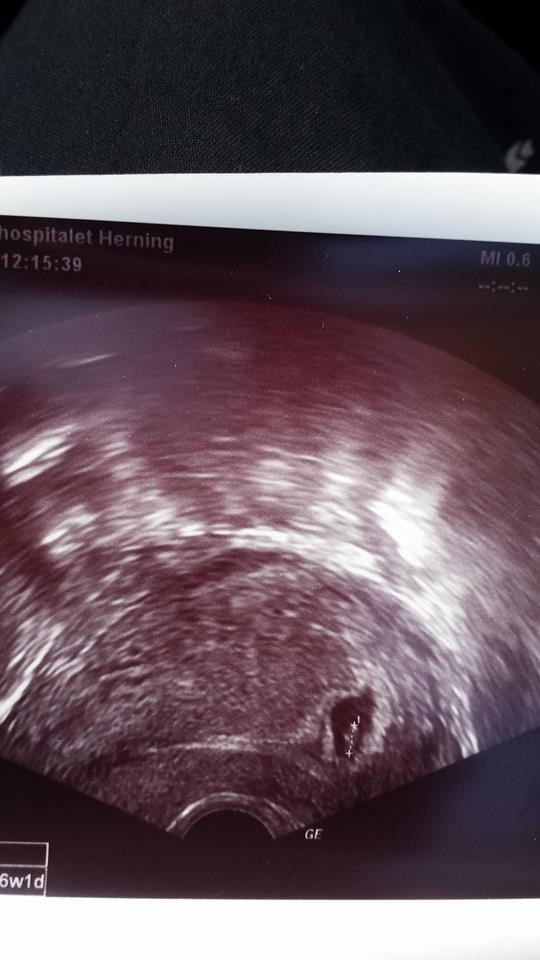

Her er min 6+1

Vedhæftede fotos (klik for at se i fuld størrelse)